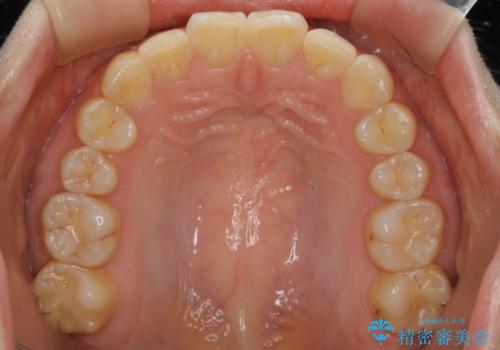

【非抜歯】ガタつきと歯軸を正して長持ちする歯へ

- 歯のガタつきと噛み合わせの改善を主訴に来院されました。

非抜歯で、少量の奥歯の移動と歯列の拡大・IPRを駆使して主訴を改善するための治療計画を立案しました。